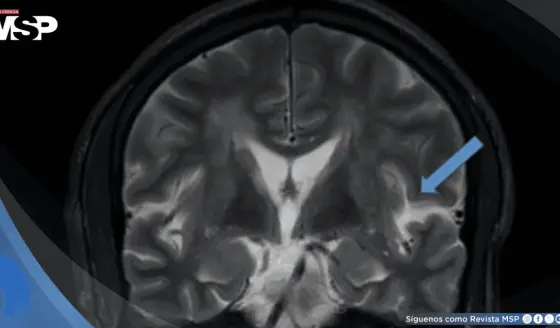

Síndrome de encefalopatía posterior reversible asociado a crisis hipertensiva con estado epiléptico